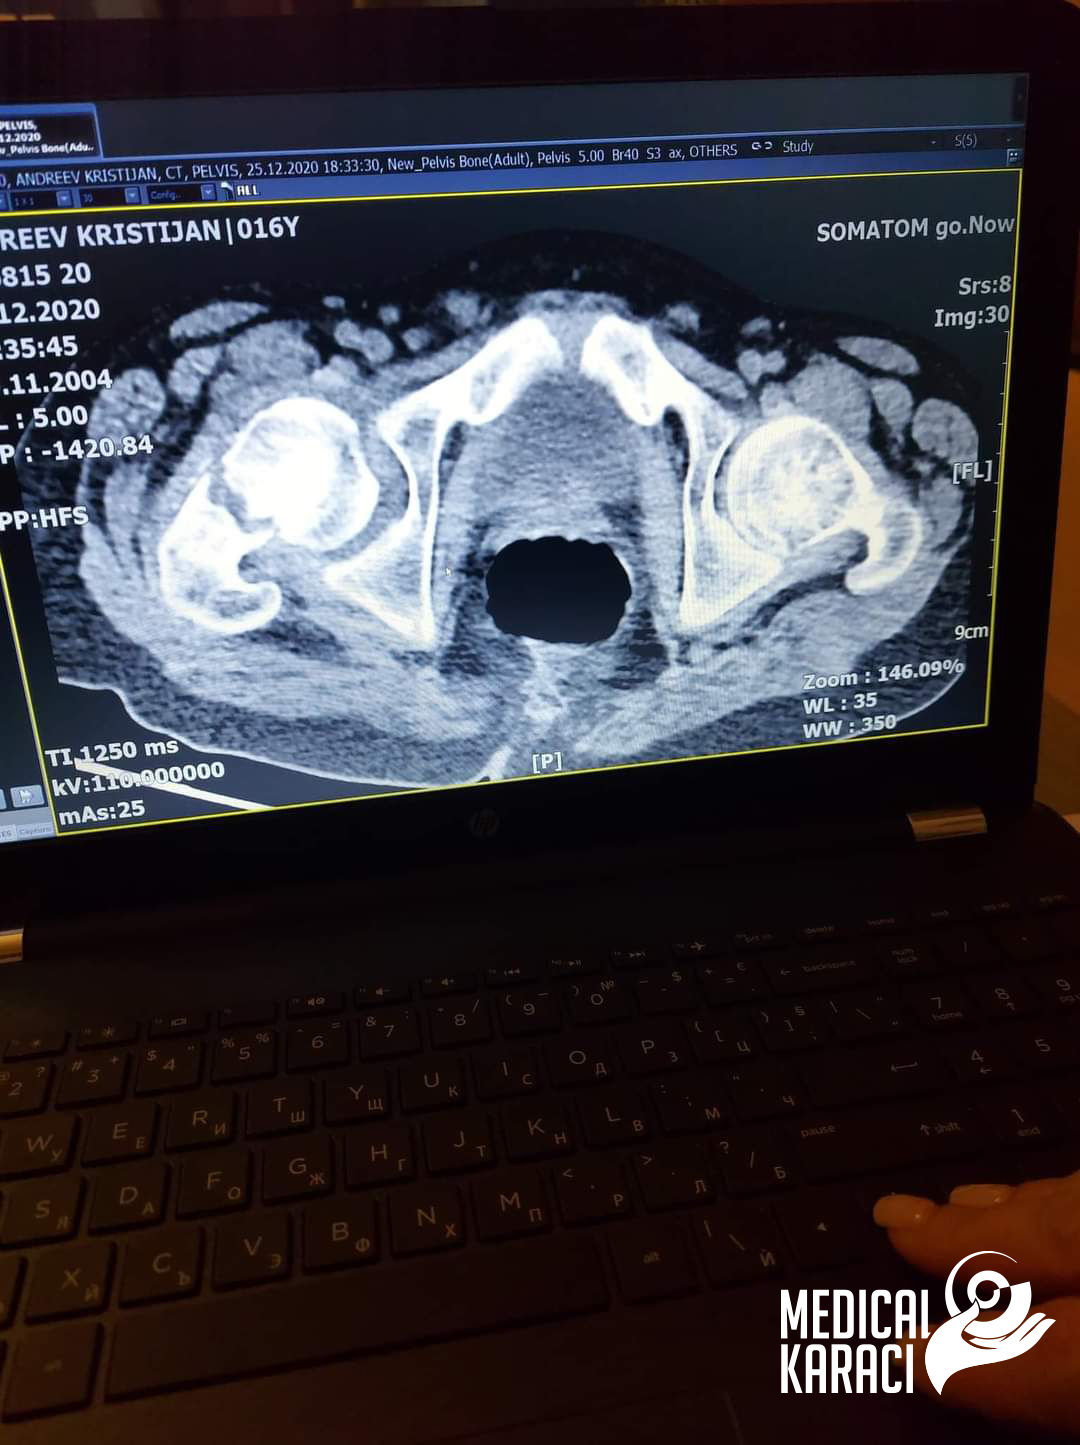

Kristijan e dete na 17 godishna vozrast koj boleduva od mnogu teshka forma na Autizam i Epilepsija, vo Dekemvri 2020 padna i go skrshi kolkot. Koga site vo Makedonija ni kazuvaa deka nemoze da go operiraat i deka nema nikogash veke da zastane na noze i da odi jas ne se otkazav, no nitu ti mila moja Zvezdelina Kara i Karaci Tours Medical denonokno istrazuvashe, go barashe i go najde najdobroto za Kristijan !! Kristijan blagodarenie na tebe i na Prof. Dr. Mustafa Kürklü ZASTANA NA NOZE I ODI 🙏🙏Neznam kako da ti se zablagodaram za se shto napravi i pravish za Kristijan, za celata organizacija vo bolnicata Memorial Bahcelievler Hospital za celo vreme shto beshe i si so nas. Zatoa shto se raduvash i se borish zaedno so nas🙏